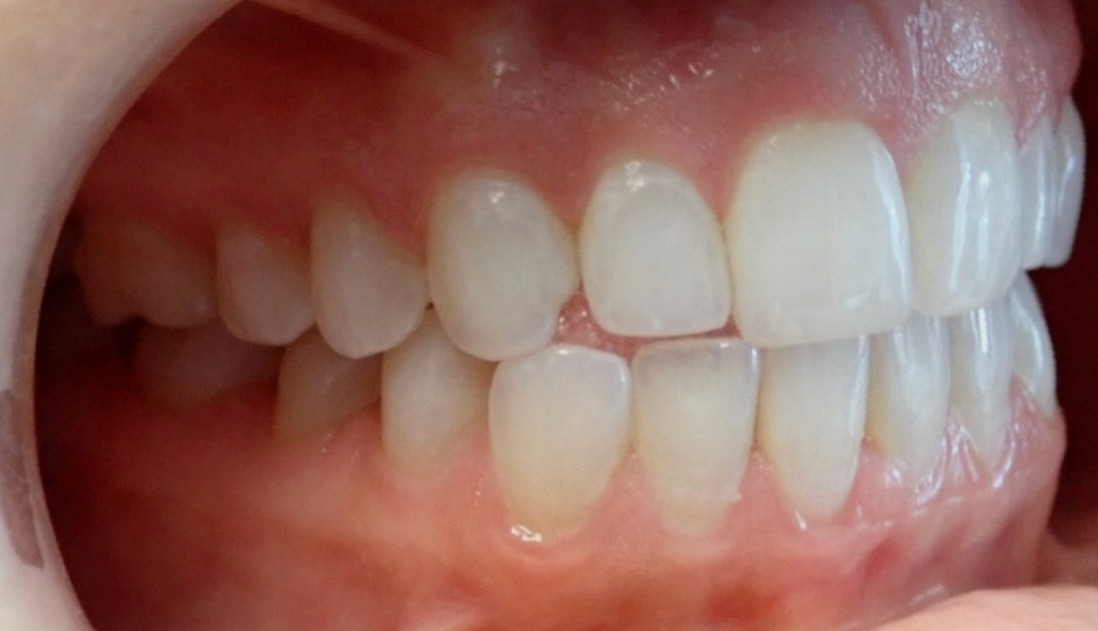

Initial treatment

INTRAORAL